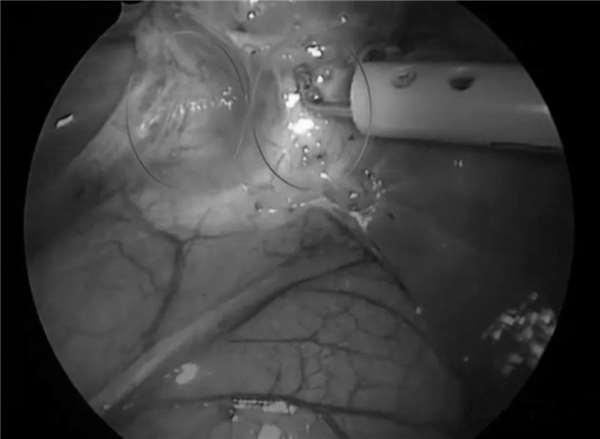

山高在最關鍵的一刻,因為自己長期以來過份擔心,行事謹慎獲得了回報,他及時發現了波琦身體的異樣之處,成功避免了一場手術事故!

最終,他剪掉了正確的靜脈,切除了波琦病變的右下半肺葉。

下一步就是要觀察剩下的肺葉能不能正常工作了,手術之後,波琦的肺部開始充滿空氣並膨脹起來,這說明手術成功了。